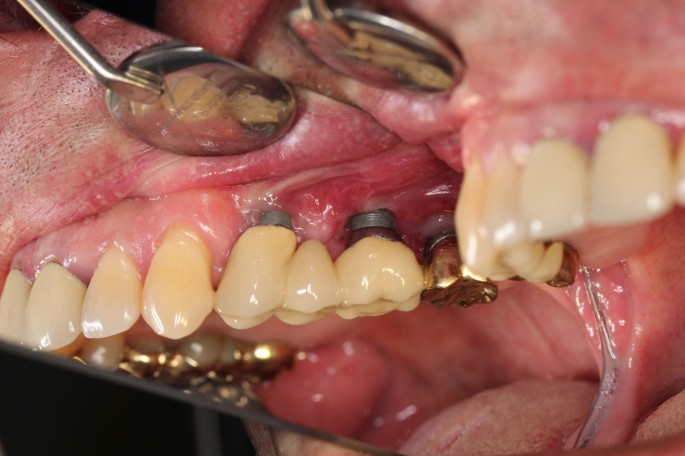

Resective therapy

In analogy to periodontitis, resective surgery has been shown to be effective in reduction of BOP, probing depths and clinical signs of inflammation. The basic principles include the elimination the periimplant osseous defect using ostectomy and osteoplasty as well as bacterial decontamination (Figures 4 and 5). Additionally, smoothening and polishing of the supracrestal implant surface (implantoplasty) may be applied.